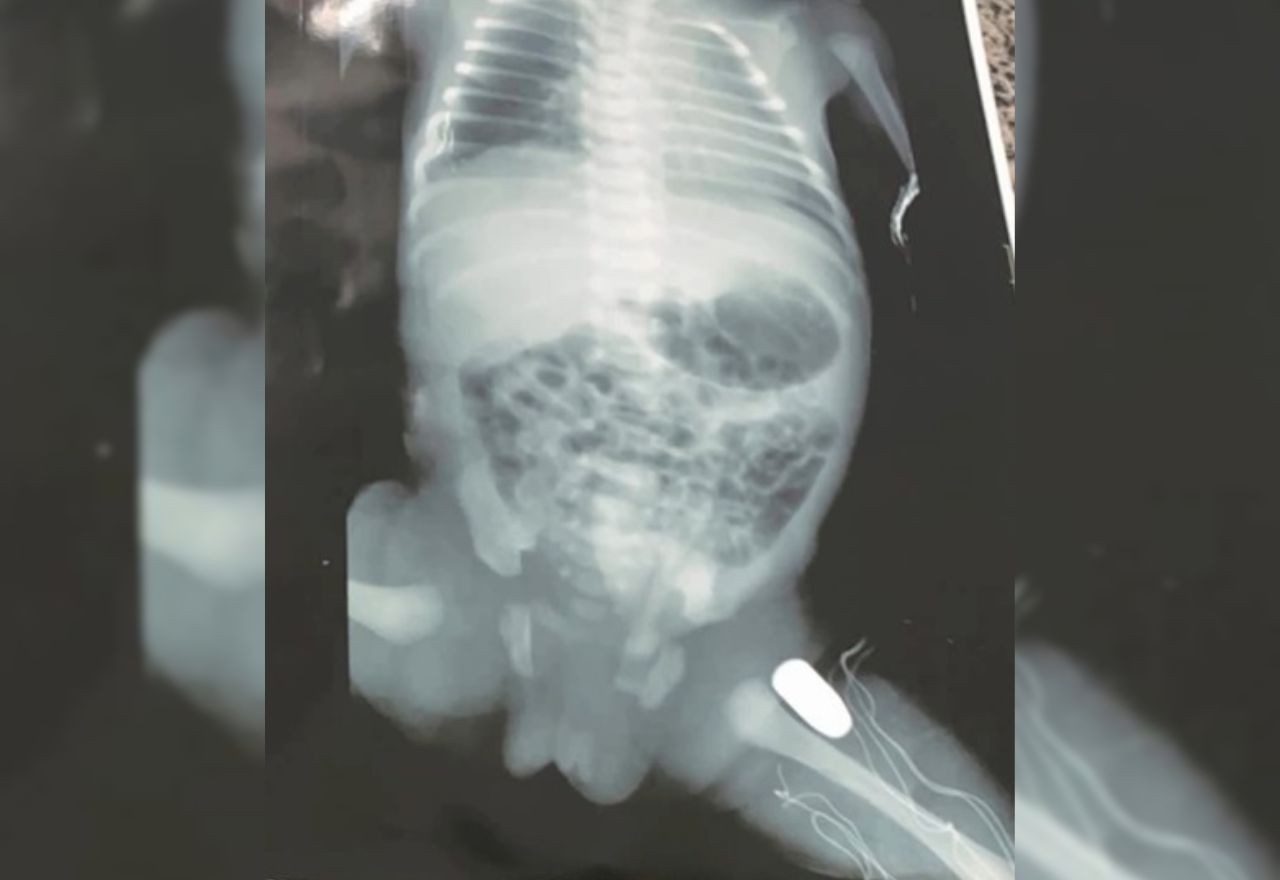

Rebeca foi socorrida para o Hospital Regional Materno Infantil de Imperatriz, onde o parto foi realizado. Exames de imagem comprovaram que a bala estava alojada na coxa esquerda da criança, mas não atingiu nenhum órgão vital. O bebê deve ser operado ainda nesta segunda-feira (17) para retirada do projétil.